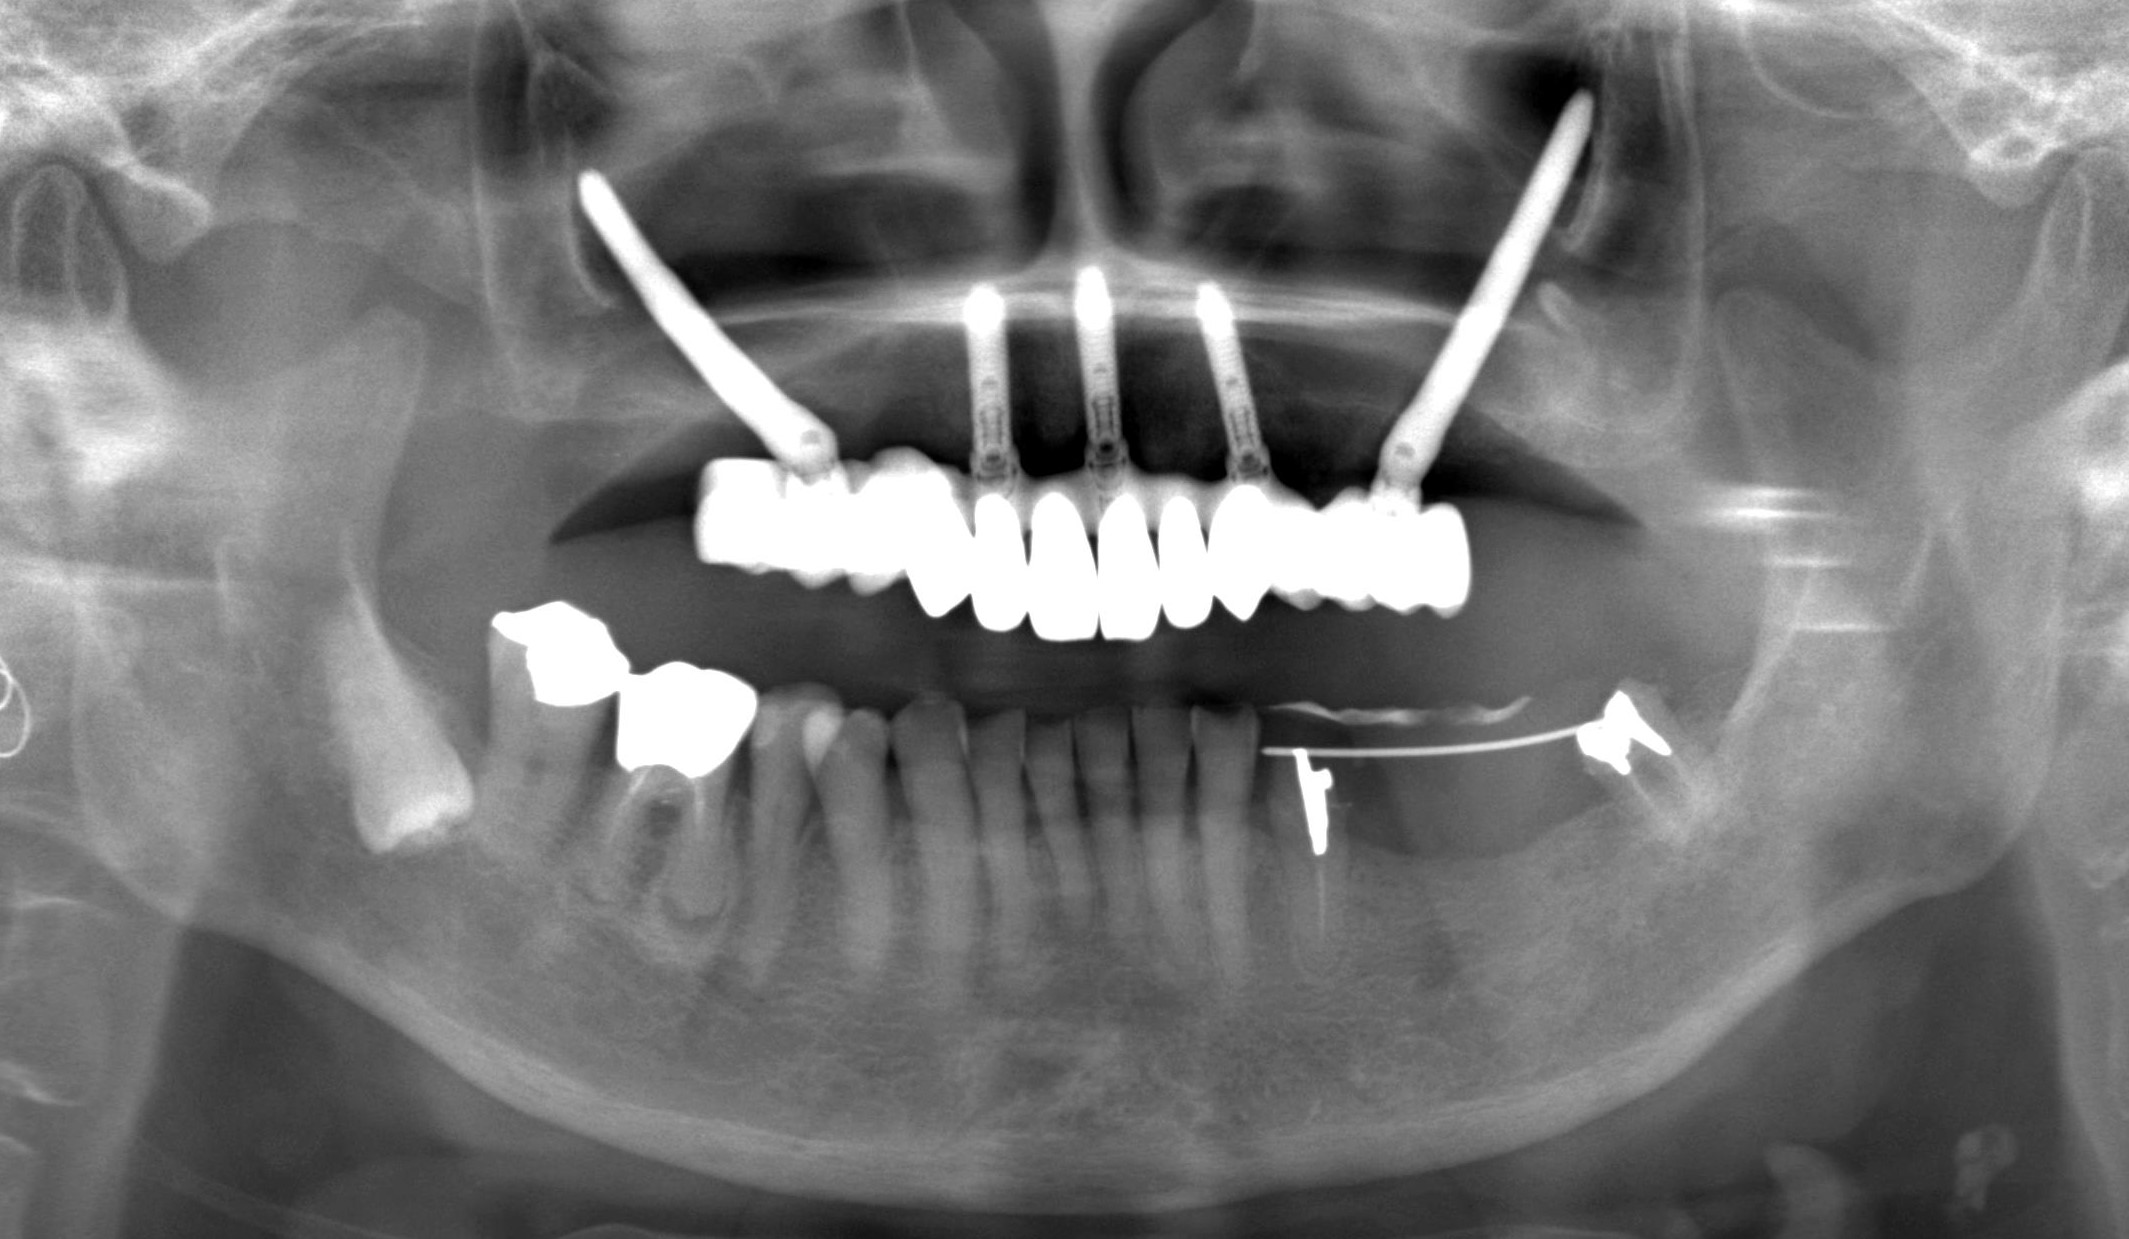

70代 女性 インプラントの難易度が高く、歯科医師の紹介で来院

治療前

治療前

治療後

治療後

治療前

治療前

治療後

治療後

治療前レントゲン

治療前レントゲン

治療後レントゲン

治療後レントゲン

治療計画(シミュレーション)

| 主訴 | インプラントの難易度が高く、歯科医師の紹介で来院。部分入れ歯を使用、ついに入れ歯をひっかける歯が痛くなり、食事がまともにできない。通常のインプラント治療では、抜歯をしてから、総入れ歯を半年以上は入れないとできないと聞いた。歯医者の息子から、手術当日に咬める歯を入れられる先生がいると聞いた。 |

|---|---|

| 年代・性別 | 70代 女性 |

| 治療部位 | 上顎6~6 |

| 治療費用 |

インプラント手術料 300,000円×5本=1,500,000円 |

| 手術回数 | 1回 |

| 治療期間 | 6ヶ月 |

| 手術時間 | 180分 |

| 治療回数 | 8回 |